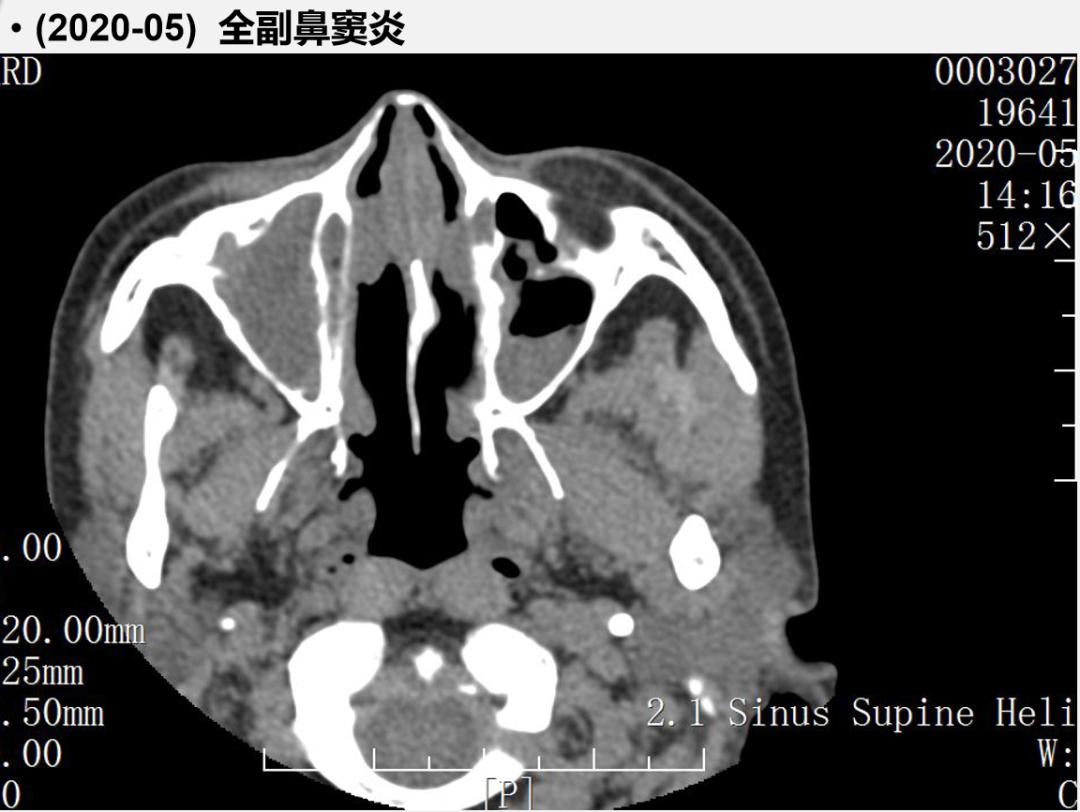

而该患者最主要的问题就是鼻窦的问题,可以看到,全副鼻窦炎造成她的嗅觉障碍。原因是什么呢?实际上她就是过敏性鼻炎反复发作,没有得到控制,从而越来越加重,造成了引流不畅。